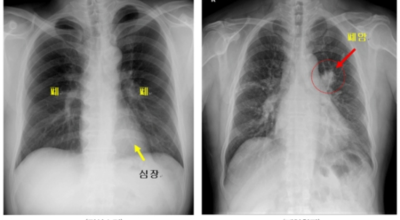

폐암이란?

폐암은 폐에 생기는 악성 종양을 말합니다. 폐에서 직접 발생하는 원발성 폐암과, 다른 장기에서 전이되어 온 전이성 폐암으로 나눌 수 있어요. 전 세계적으로 매년 약 130만 명이 폐암으로 사망하는데, 이는 암으로 인한 사망 원인 중 가장 높은 비중을 차지하고 있습니다.